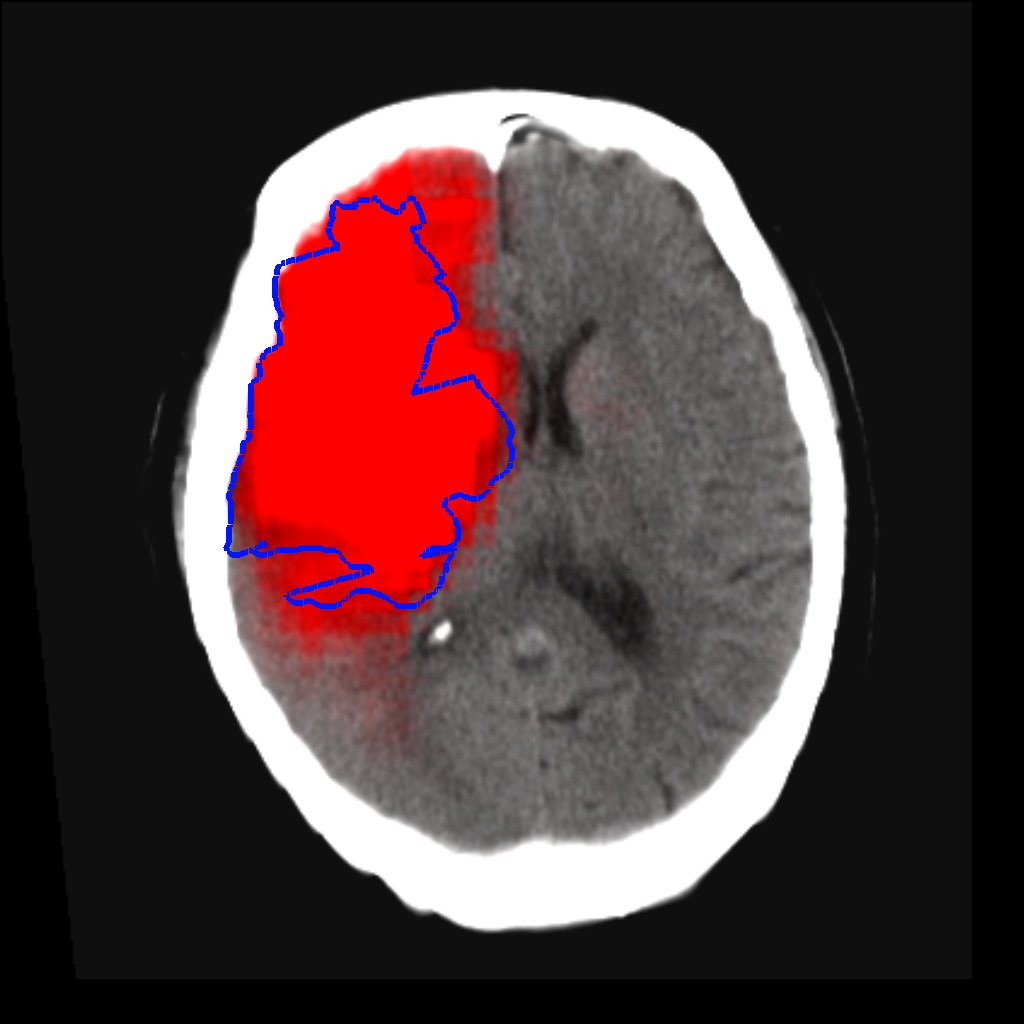

Fig. 3 shows a scatter plot and a Bland-Altman plot of the true and predicted volumes for all subjects in the testing folds using the proposed method. The mean volume error is -2.8 ml (the prediction is a slight underestimation) and the mean absolute volume error is 36.7 ml. The mean Dice score is 0.48. A representative set of predictions is shown in Fig. 4.